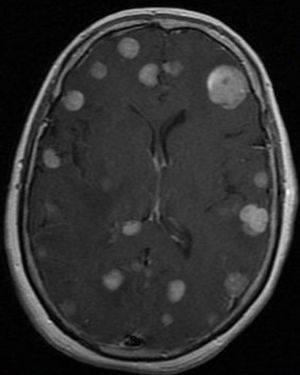

What sequence do you use post contrast for brain mets MR Imaging?